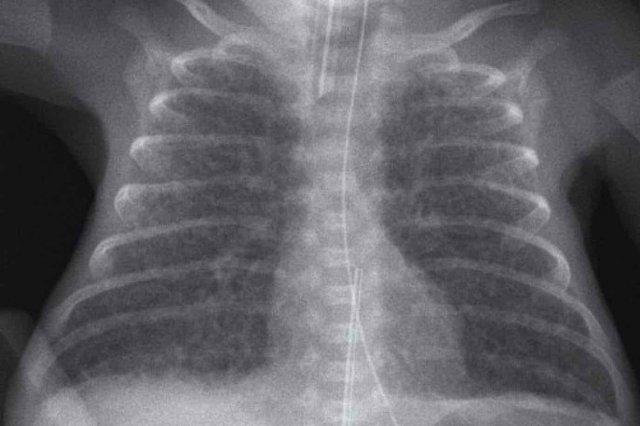

One day old neonate, 26 weeks of gestational age.

Image

- Granular opacification of both lungs.

- Vessels and cardiac silhouette are hard to distinguish.

- Umbilical venous line properly positioned.

- Vị trí đặt catheter động mạch rốn quá sâu, cần rút lại đến mức T6.

- NG tube in situ.

Conclusion: RDS grade 3.